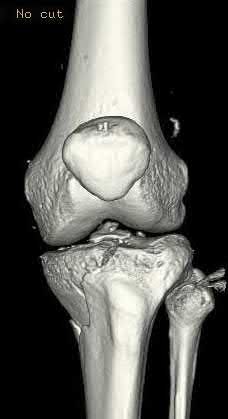

A 38-year-old male suffers the injury shown in Figure A. During operative fixation, free osteoarticular fragments are encountered and reconstruction of these pieces is attempted. Postoperatively, which of the following will have the most beneficial effect on the healing potential of the surviving chondrocytes within these reconstructed articular segments?

Figure A demonstrates a comminuted tibial plateau fracture with significant intra-articular involvement. Basic science evidence has demonstrated that post-operative gentle compressive loading may have a positive impact on articular cartilage healing; however, excessive shear loading may be detrimental.

Irrgang et al provide guidelines for rehabilitation following surgical management of articular cartilage lesions of the knee. They state that after articular cartilage repair, exercises to enhance muscle function must be done in a manner which minimizes shear loading of the joint surfaces in the area of the lesion. The authors also discuss the benefits of gentle compressive loading and motion of the joint, and its positive effects on chondrocyte nutrition.

Furthermore, they recommend a period of protected weight bearing as often being necessary, and that this should be followed by progressive loading of the joint.